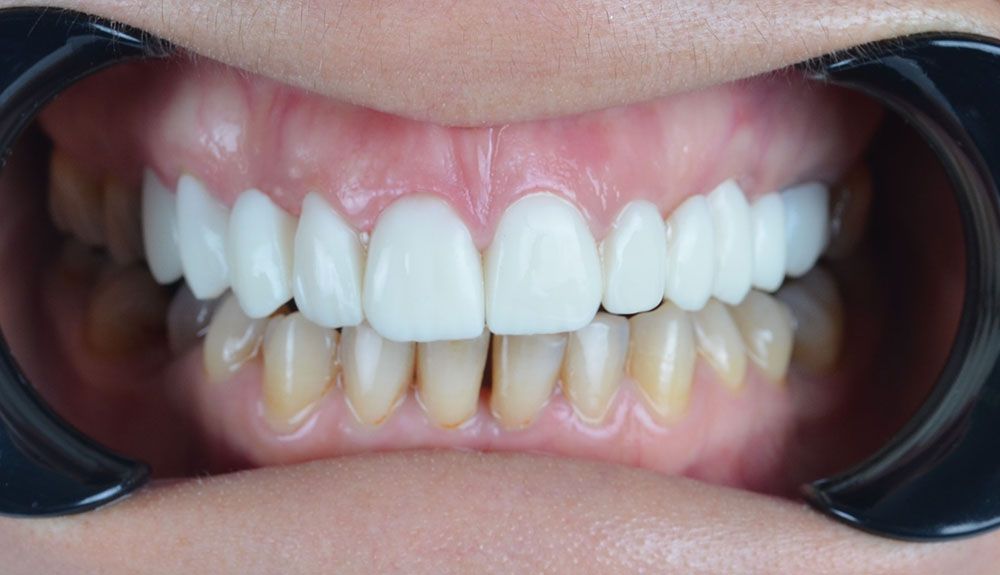

Our lab send us a model that shows us the final form of her teeth after 3 days. We showed it to our patient and she liked the final result. So after she confirm the treatment we decided to start with periodontal treatment and gingivectomy. After 7 days of healing, we started preperations and took our impressions to send it back to the lab. The lab produced the same teeth we showed our patient before by replicating the previous teeth design. So our patient had the teeth we showed her before by only waiting 3 more days and also for some extra cost. But the result was for good.

I was not satisfied with my crowns that I had used before and I thought that they should be changed and I should use more natural crowns. I started to do research on the internet. When I found this place, they said that my gums might have problems and that's why my pain might be because of this. When I came to the clinic, we learnt that I had inflammation in my gums. Gum treatment was started quickly. first they made a proving and although it was a trial, it was very nice. After my recovery was complete, I went again and they took my impression. I had even more beautiful teeth than in the trial.